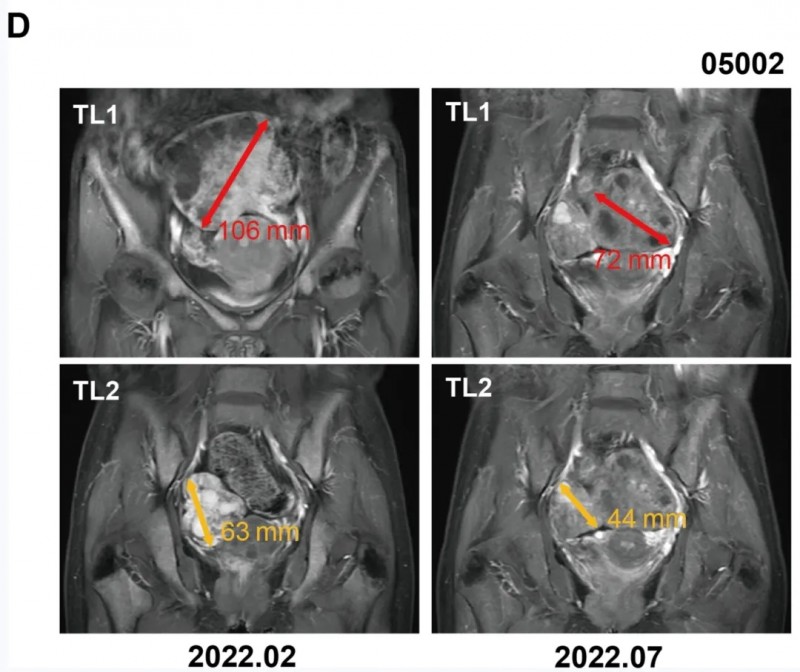

《Science Advances》曾报道一则晚期胃癌治疗奇迹:52岁女性患者确诊晚期胃癌伴卵巢植入转移,此前已接受信迪利单抗、白蛋白紫杉醇、Tegio、EOX及FOLFIRI等多线治疗,但因肿瘤负荷巨大,病情持续进展,预计总生存期仅3~6个月。

2022年2月3日起,患者接受LPP-PCVmRNA疫苗联合维多珠单抗、派姆单抗的治疗方案,奇迹般实现8.4个月的无进展生存期(PFS)。治疗期间,患者达到部分缓解(PR),影像学检查显示肿瘤体积较治疗前明显缩小:基线时目标病变最大直径为178mm,治疗第6个月缩小至107mm(详见下图)。